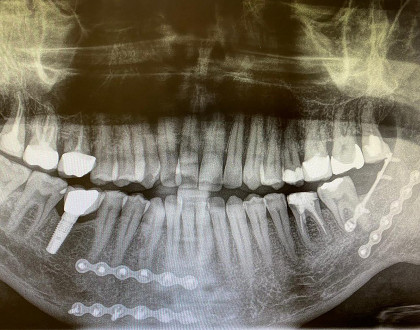

Արթուր Աբրահամի ծնոտի ռենտգենն է՝ մենամարտից հետո մետաղներով հավաքած